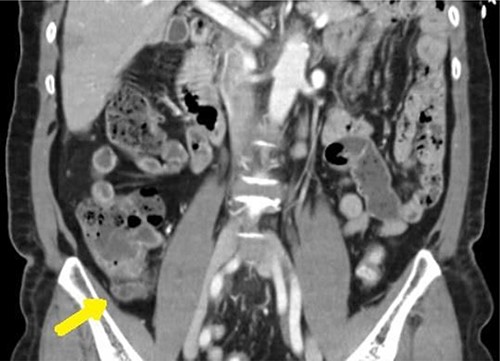

A 65-year-old female with a past medical history of hyperlipidemia presented to the emergency department with 1 day of right lower quadrant (RLQ) abdominal pain. These symptoms were confirmed on physical examination as moderately tender to palpation. Clinical assessment was otherwise unremarkable. Yet, a computed tomography (CT) was obtained confirming high suspicion for acute appendicitis with an enlarged appendix of 9 mm and associated with wall enhancement and evidence of fat stranding (see Fig. 1).